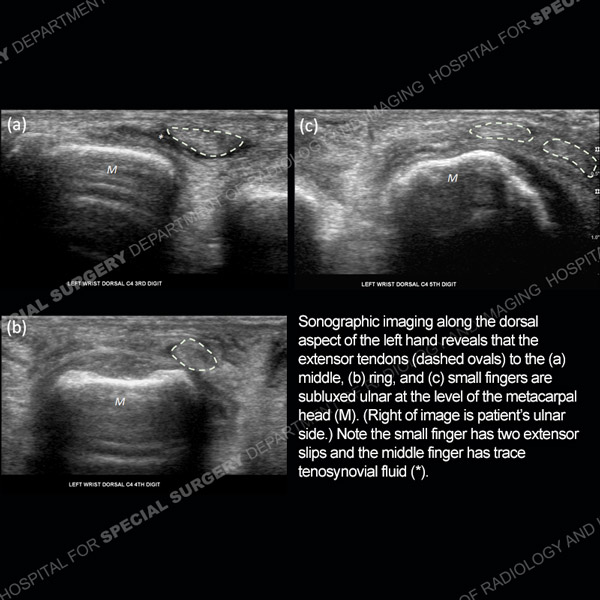

![]() |

Featured Ultrasound of the Month Case |